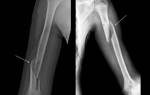

Диагностика

Ключевым методом диагностики служит обзорная рентгенография коленного сустава, выполняемая в двух проекциях. В дополнение к этому могут быть использованы компьютерная томография и магнитно-резонансная томография.